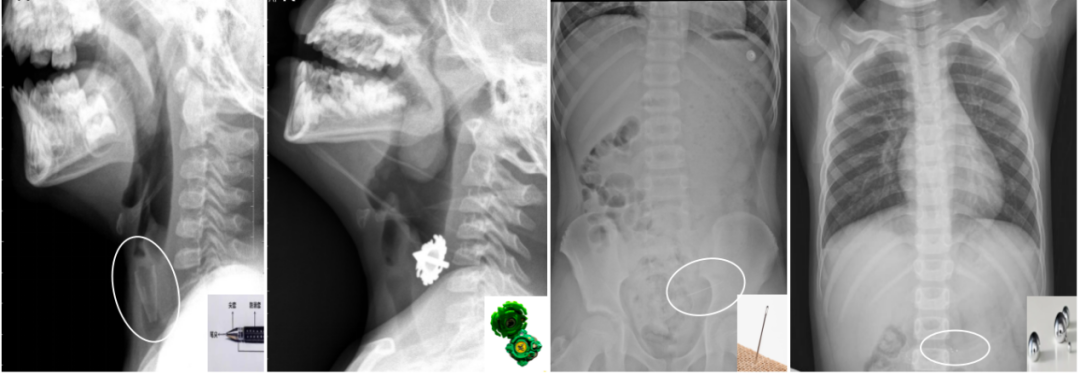

孩子误吞的异物五花八门,常见的有硬币、纽扣电池、小玩具、发卡等。

X线能够清晰显示那些“不透X线”的物体,也就是在影像中呈现为白色高密度的异物。例如:

①金属类物品:如硬币、别针、钥匙扣;

②较大或较厚的玻璃、陶瓷;

③部分塑料和橡胶制品:如玩具零件、纽扣电池(需紧急处理!)

呼吸道异物(左1笔帽、左2陀螺)、消化道异物(左3细针、左4水银)